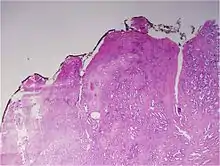

Gleason grade — Lower grades are associated with small, closely packed glands. Cells spread out and lose glandular architecture as grade increases. Gleason score is calculated from grade as described in the text. |

The Gleason grading system is used to help evaluate the prognosis of men with prostate cancer using samples from a prostate biopsy. Together with other parameters, it is incorporated into a strategy of prostate cancer staging which predicts prognosis and helps guide therapy. A Gleason score is given to prostate cancer based upon its microscopic appearance.[1]

A pathologist microscopically examines the biopsy specimen for certain "Gleason" patterns. These Gleason patterns are associated with the following features:

- Pattern 1 - The cancerous prostate closely resembles normal prostate tissue. The glands are small, well-formed, and closely packed. This corresponds to a well differentiated carcinoma.

- Pattern 2 - The tissue still has well-formed glands, but they are larger and have more tissue between them, implying that the stroma has increased. This also corresponds to a moderately differentiated carcinoma.

- Pattern 3 - The tissue still has recognizable glands, but the cells are darker. At high magnification, some of these cells have left the glands and are beginning to invade the surrounding tissue or having an infiltrative pattern. This corresponds to a moderately differentiated carcinoma.

- Pattern 4 - The tissue has few recognizable glands. Many cells are invading the surrounding tissue in neoplastic clumps. This corresponds to a poorly differentiated carcinoma.

- Pattern 5 - The tissue does not have any or only a few recognizable glands. There are often just sheets of cells throughout the surrounding tissue. This corresponds to an anaplastic carcinoma.

In the present form of the Gleason system, prostate cancer of Gleason patterns 1 and 2 are rarely seen. Gleason pattern 3 is by far the most common.

The Gleason grade is based on tissue architectural patterns rather than purely cytological changes. These tissue patterns are classified into 5 grades, numbered 1 though 5. Lower numbers indicate more differentiation, with pattern 5 being the least differentiated.[4][7] Differentiation is the degree to which the tissue, in this case the tumor, resembles native tissue. Greater resemblance (lower grade) is typically associated with a better prognosis.

Cytological differences between normal prostate and neoplastic glands are evident in changes to the typical two cell layers of the gland. In prostatic adenocarcinoma, the basal (bottom, usually cuboidal type) cell layer is lost, with only the top layer (usually columnar to pseudostratified) remaining.

Gleason pattern 1 is the most well-differentiated tumor pattern. It is a well-defined nodule of single/separate, closely/densely packed, back-to-back gland pattern that does not invade into adjacent healthy prostatic tissue. The glands are round to oval shaped and proportionally large, compared to Gleason pattern 3 tumors, and are approximately equal in size and shape to one another.[4][7]

Gleason 2 is fairly well-circumscribed nodules of single, separate glands. However, the glands are looser in arrangement and not as uniform as in pattern 1. Minimal invasion by neoplastic glands into the surrounding healthy prostate tissue may be seen. Similar to Gleason 1, the glands are usually larger than those of Gleason 3 patterns, and are round to oval in shape. Thus the main difference between Gleason 1 and 2 is the density of packing of the glands seen; invasion is possible in Gleason 2, but by definition not in Gleason 1.[4][7]

Gleason 3 is a clearly infiltrative neoplasm, with extension into adjacent healthy prostate tissue. The glands alternate in size and shape, and are often long/angular. They are usually small/micro-glandular in comparison to Gleason 1 or 2 grades. However, some may be medium to large in size. The small glands of Gleason 3, in comparison to the small and poorly defined glands of pattern 4, are distinct glandular units. Mentally you could draw a circle around each of the glandular units in Gleason 3.[4][7]

Gleason pattern 4 glands are no longer single/separated glands like those seen in patterns 1-3. They look fused together, difficult to distinguish, with rare lumen formation vs Gleason 1-3 which usually all have open lumens (spaces) within the glands, or can be cribriform-(resembling the cribriform plate/similar to a sieve: an item with many perforations). Fused glands are chains, nests, or groups of glands that are no longer entirely separated by stroma-(connective tissue that normally separates individual glands in this case). Fused glands contain occasional stroma giving the appearance of "partial" separation of the glands. Due to this partial separation, fused glands sometimes have a scalloped (think looking at a slice of bread with bite taken out of it) appearance at their edges.[4][7]

Neoplasms have no glandular differentiation (thus not resembling normal prostate tissue at all). It is composed of sheets (groups of cells almost planar in appearance (like the top of a box), solid cords (group of cells in a rope like fashion running through other tissue/cell patterns seen), or individual cells. You should not see round glands with lumenal spaces that can be seen in the other types that resemble more the normal prostate gland appearance.[4][7]